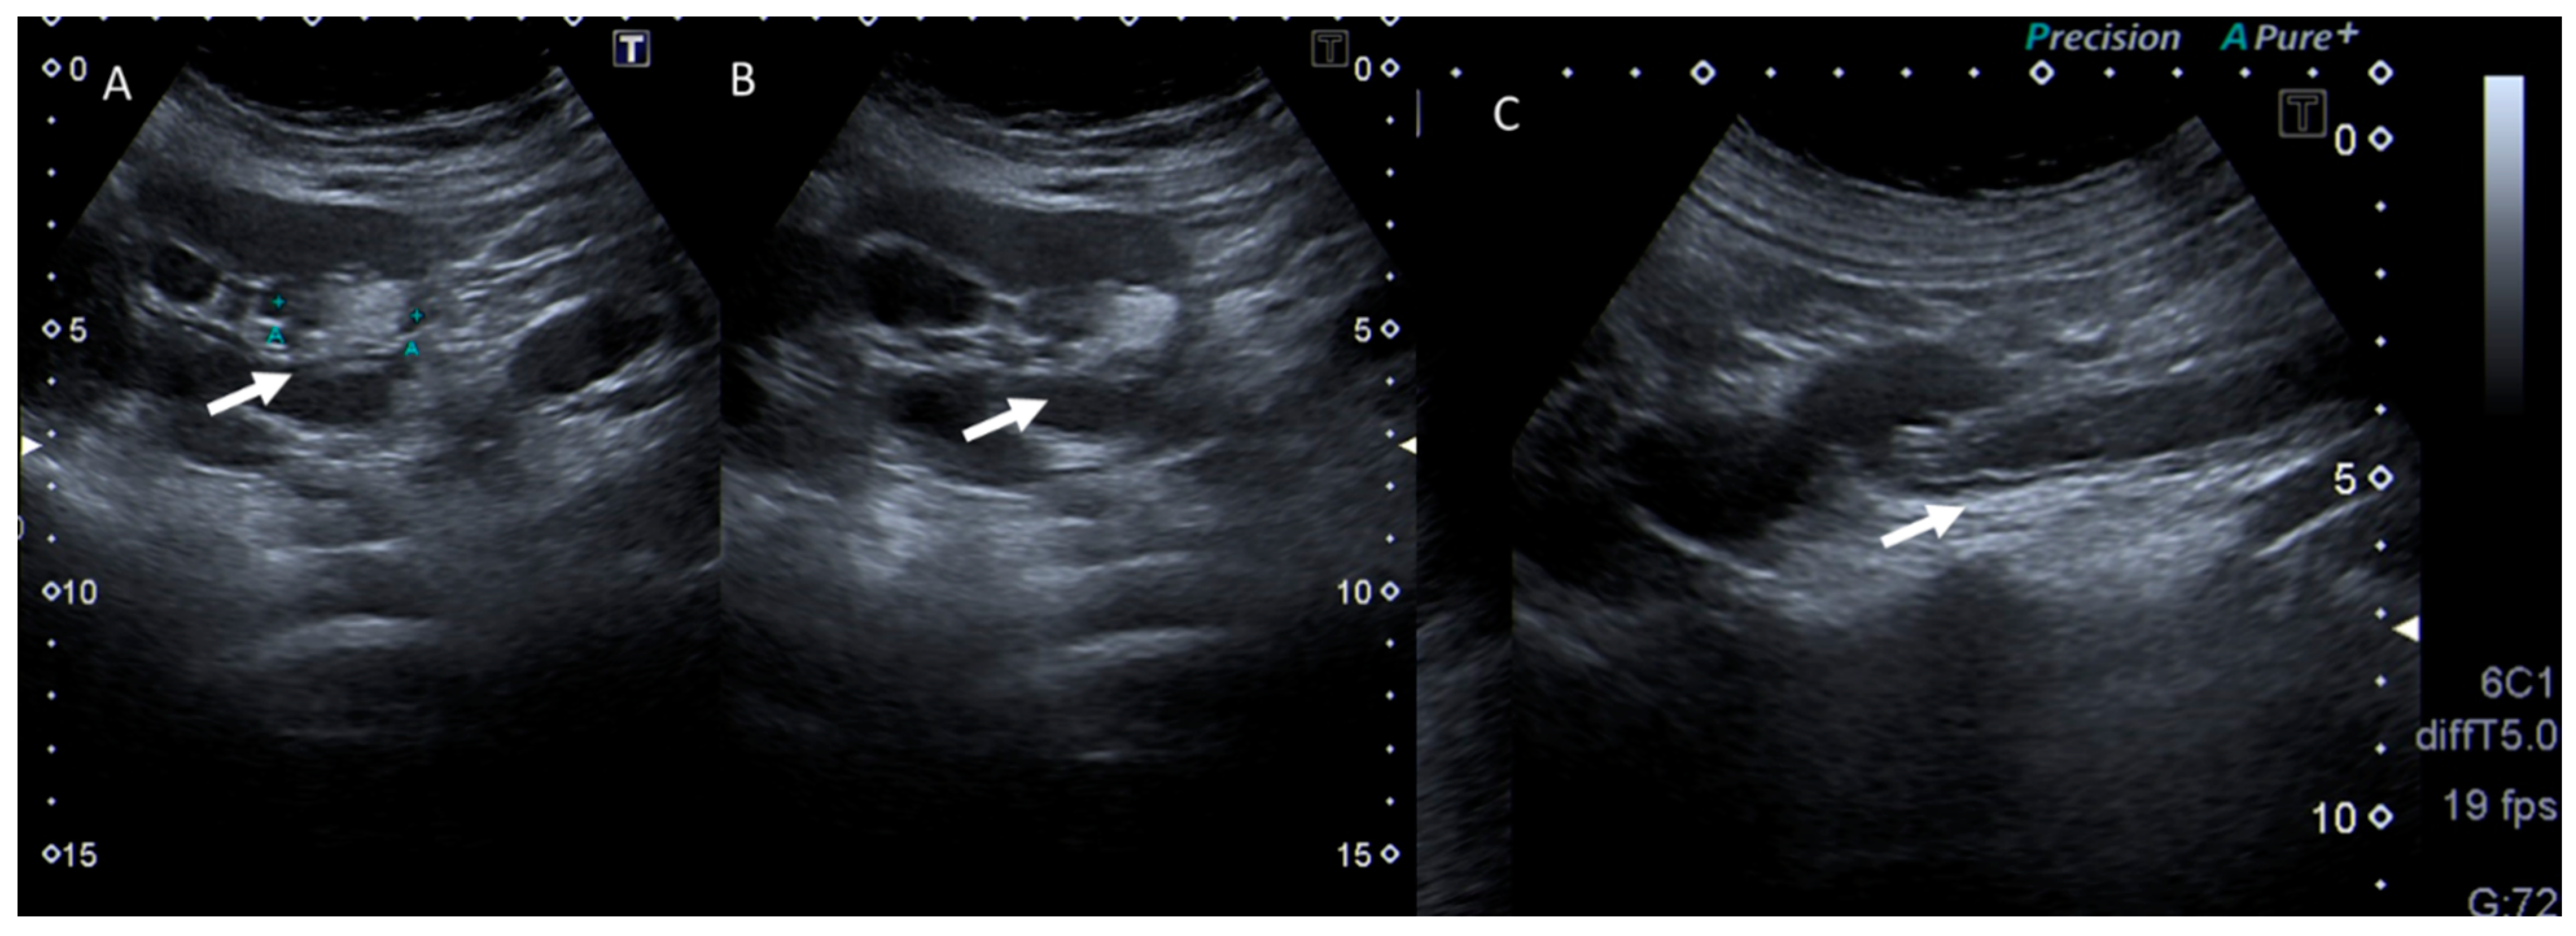

Figure 3.

Pregnant woman with left flank pain. US assessment (A,B) shows hydroureteronephrosis (arrow) in (A) and distal ureteral calculi (arrow) in (B).